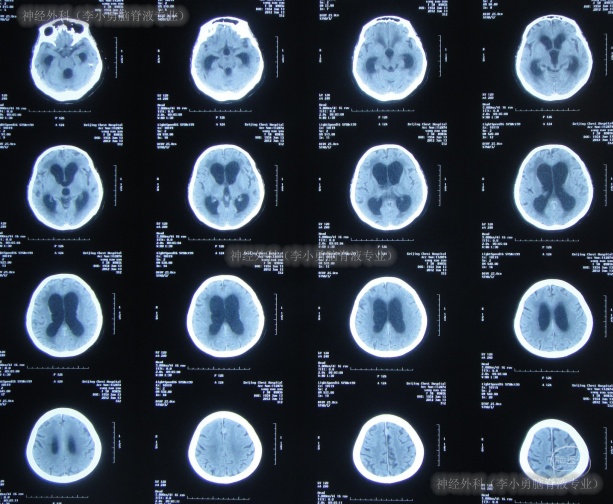

2012年6月14日,入院时:昏迷、体温很高、鼻饲、睡眠差,保留导尿(图-11)。入院后完善血、尿常规、生化全项、胸片、心电图等检查后病情危重,下病危通知。查头颅CT示脑积水(图-12)。

图-12:2012年6月14日头颅CT